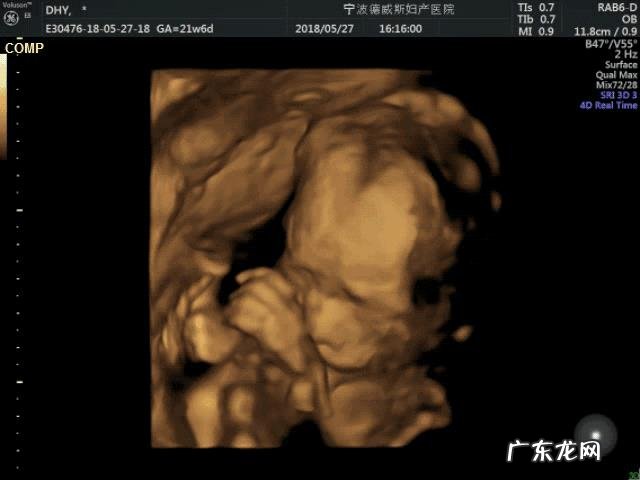

到了20周这样,就可以去医院做大排畸了,这个大排畸就是三维和四维彩超了,主要观察胎儿的外形,检查胎儿身体是否有疾病和和存在隐患,这个大排畸一定要做,非常重要 。